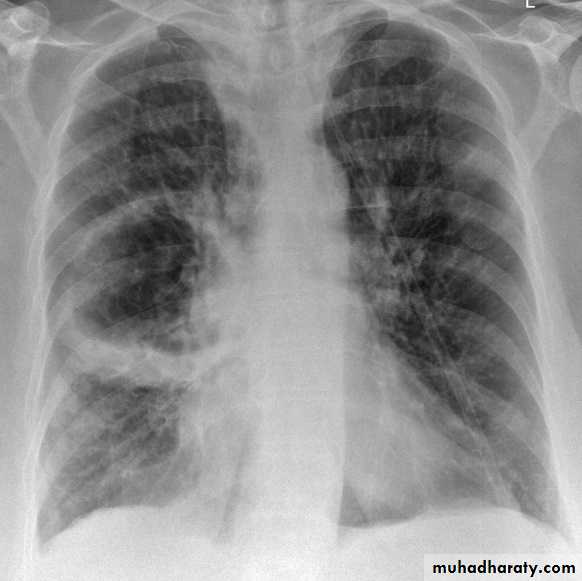

RT ULC

LT L L collapse

RT middle lobe collapse

RT L L collapse